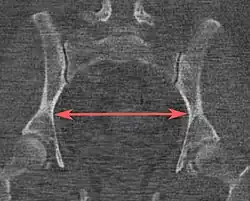

Tomografias computadorizadas de baixa dose em 3D podem ser usadas para estimar os principais parâmetros da pelvimetria:[4]

| Distância interespinhosa |

|

Plano axial |

A linha entre os pontos ósseos mais próximos das espinhas isquiáticas | 9,5 a 11,5 cm.[6] | |